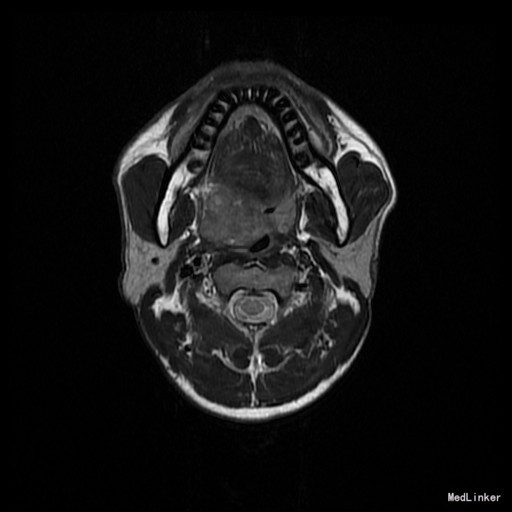

患者:男,42岁 主诉:发现右侧软腭肿物7年余。 病史:患者诉7年余前发现右侧软腭肿物,渐进性增大,无咽痛邓特殊不适。

查体:右侧软腭至硬腭处见一肿物,约5*3cm,质硬,固定,边界欠清,表面粘膜光滑。 辅助检查:外院颌面CT提示:右侧软腭实性占位,并累及鼻咽、口咽壁,建议MRI增强检查。

入院诊断:咽旁肿物(右侧软腭肿物性质待查) 治疗:入院后咽部MRI示:软腭右部软组织肿块,性质待定,鼻咽腔及口咽腔明显变窄。,未见手术禁忌,遂于全麻下行“右侧咽旁间隙肿物切除术”,术程顺利,术后未见并发症。病理:多形性腺瘤。